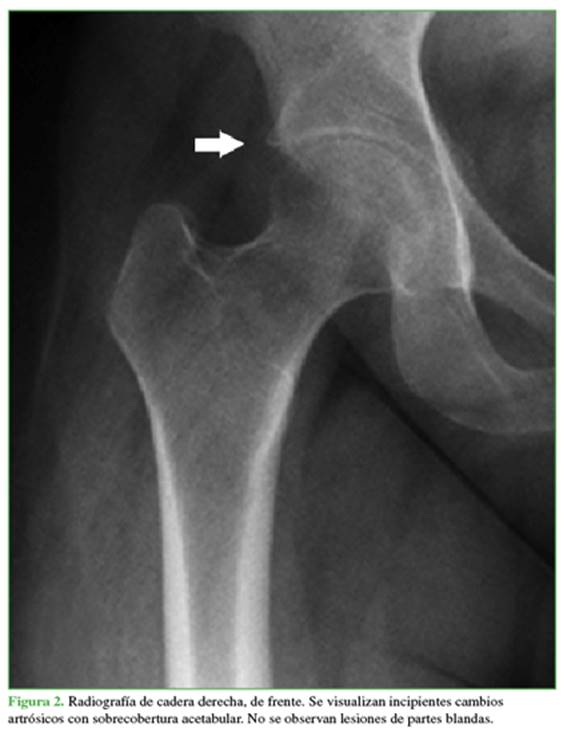

Se solicitan radiografías panorámica de pelvis (Figura 1) y de cadera derecha, de frente (Figura 2).

Las radiografías panorámica de pelvis y de cadera derecha, de frente muestran incipientes cambios artrósicos con mínima sobrecobertura acetabular. No se visualizan lesiones líticas ni blásticas.